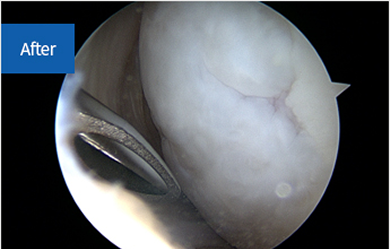

관절 내시경으로 본 정상 십자인대

십자인대파열 치료방법

십자인대파열은 초기에 보조기나 부목 착용으로 추가적인 손상을 방지하고,

안정기에는 수술을 통해 인대를 재건하거나 봉합

합니다.